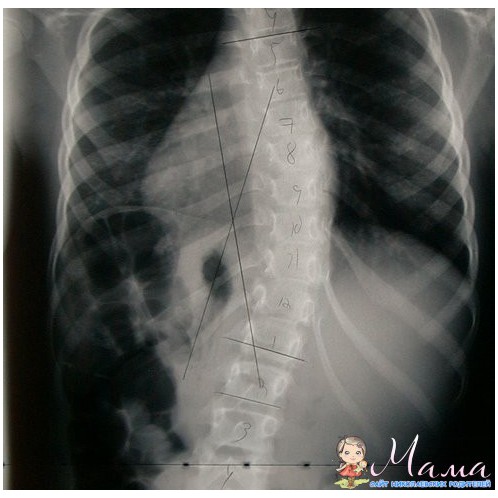

1-2-3 стадии сколиоза лечатся консервативным путем (без операции).

Лечебные программы в нашем салоне обычно включают глубокий лечебный массаж, при котором ослабленные мышцы массируются по тонизирующей методике, а напряженные - по релаксационной. Также назначается рефлексотерапия и постизометрическая релаксация мышц.